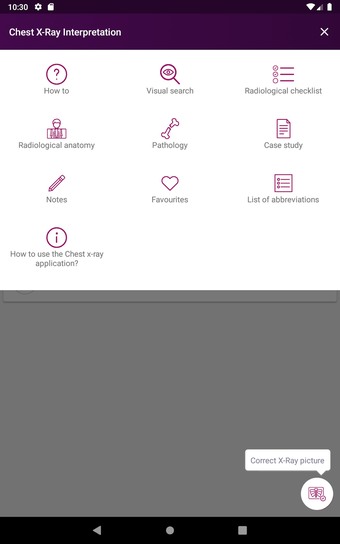

Radioloji'yi Keşfet: Göğüs Röntgeni Yorumlama, göğüs röntgeninin yorumlanmasının anlaşılmasını artırmak için tasarlanmış bir eğitim uygulamasıdır ve doktorlar, tıp öğrencileri ve radyologlar tarafından kullanılması amaçlanmaktadır. Uygulama, en küçük detayları görüntülemek için yakınlaştırılabilecek yüksek kaliteli görüntüler ve her bulgunun önemini anlamanıza yardımcı olacak bir sesli yorum içerir.

Uygulamanın amacı, kullanıcıların farklı x-ışını bulgularını ve bunların bir hastalığın teşhisinde nasıl kullanılabileceğini daha iyi anlamalarına yardımcı olmaktır. Uygulama, göğüs röntgeni yorumlaması için gerekli çeşitli yapı taşlarını kapsayan 5 bölüme ayrılmıştır.

Ayrıca, uygulama bir hastanın göğüs röntgenini incelemeleri sırasında başvurabilecekleri bir dizi nasıl yapılır içerir. Uygulamadaki nasıl yapılır adımlarını takip ederek, kullanıcılar birçok farklı bulguyu doğru bir şekilde tanımlayabilecekler ve her birini bir hastalığın teşhisi için nasıl doğru bir şekilde kullanacaklarını öğrenebileceklerdir.